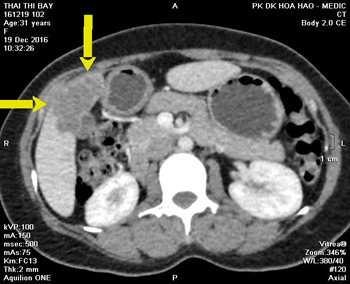

Trong lần tái khám 2 tuần tiếp theo sau đó, xét nghiệm máu bạch cầu ái toan trở về bình thường (2,5%), men gan AST và ALT trong giới hạn bình thường, chỉ có GGT còn tăng 160 IU/L, chụp lại MSCT bụng để kiểm tra diễn tiến tổn thương ở gan và đại tràng. Trên hình ảnh MSCT cho thấy tổn thương gan thay đổi ít so với lần chụp trước (đến thời điểm này mới 1 tháng kể từ khi dùng thuốc). Tuy nhiên, tổn thương ở đại tràng ngang diễn tiến rất tốt, thành chỉ còn 8mm (so với 20mm trong lần chụp trước) (Hình 5).

Hình 5a. Áp xe nhu mô gan (P) chưa thay đổi nhiều (sau 4 tuần) và Hình 5b. Tổn thương thành đại tràng ngang đã giảm rõ rệt trong lần tái khám